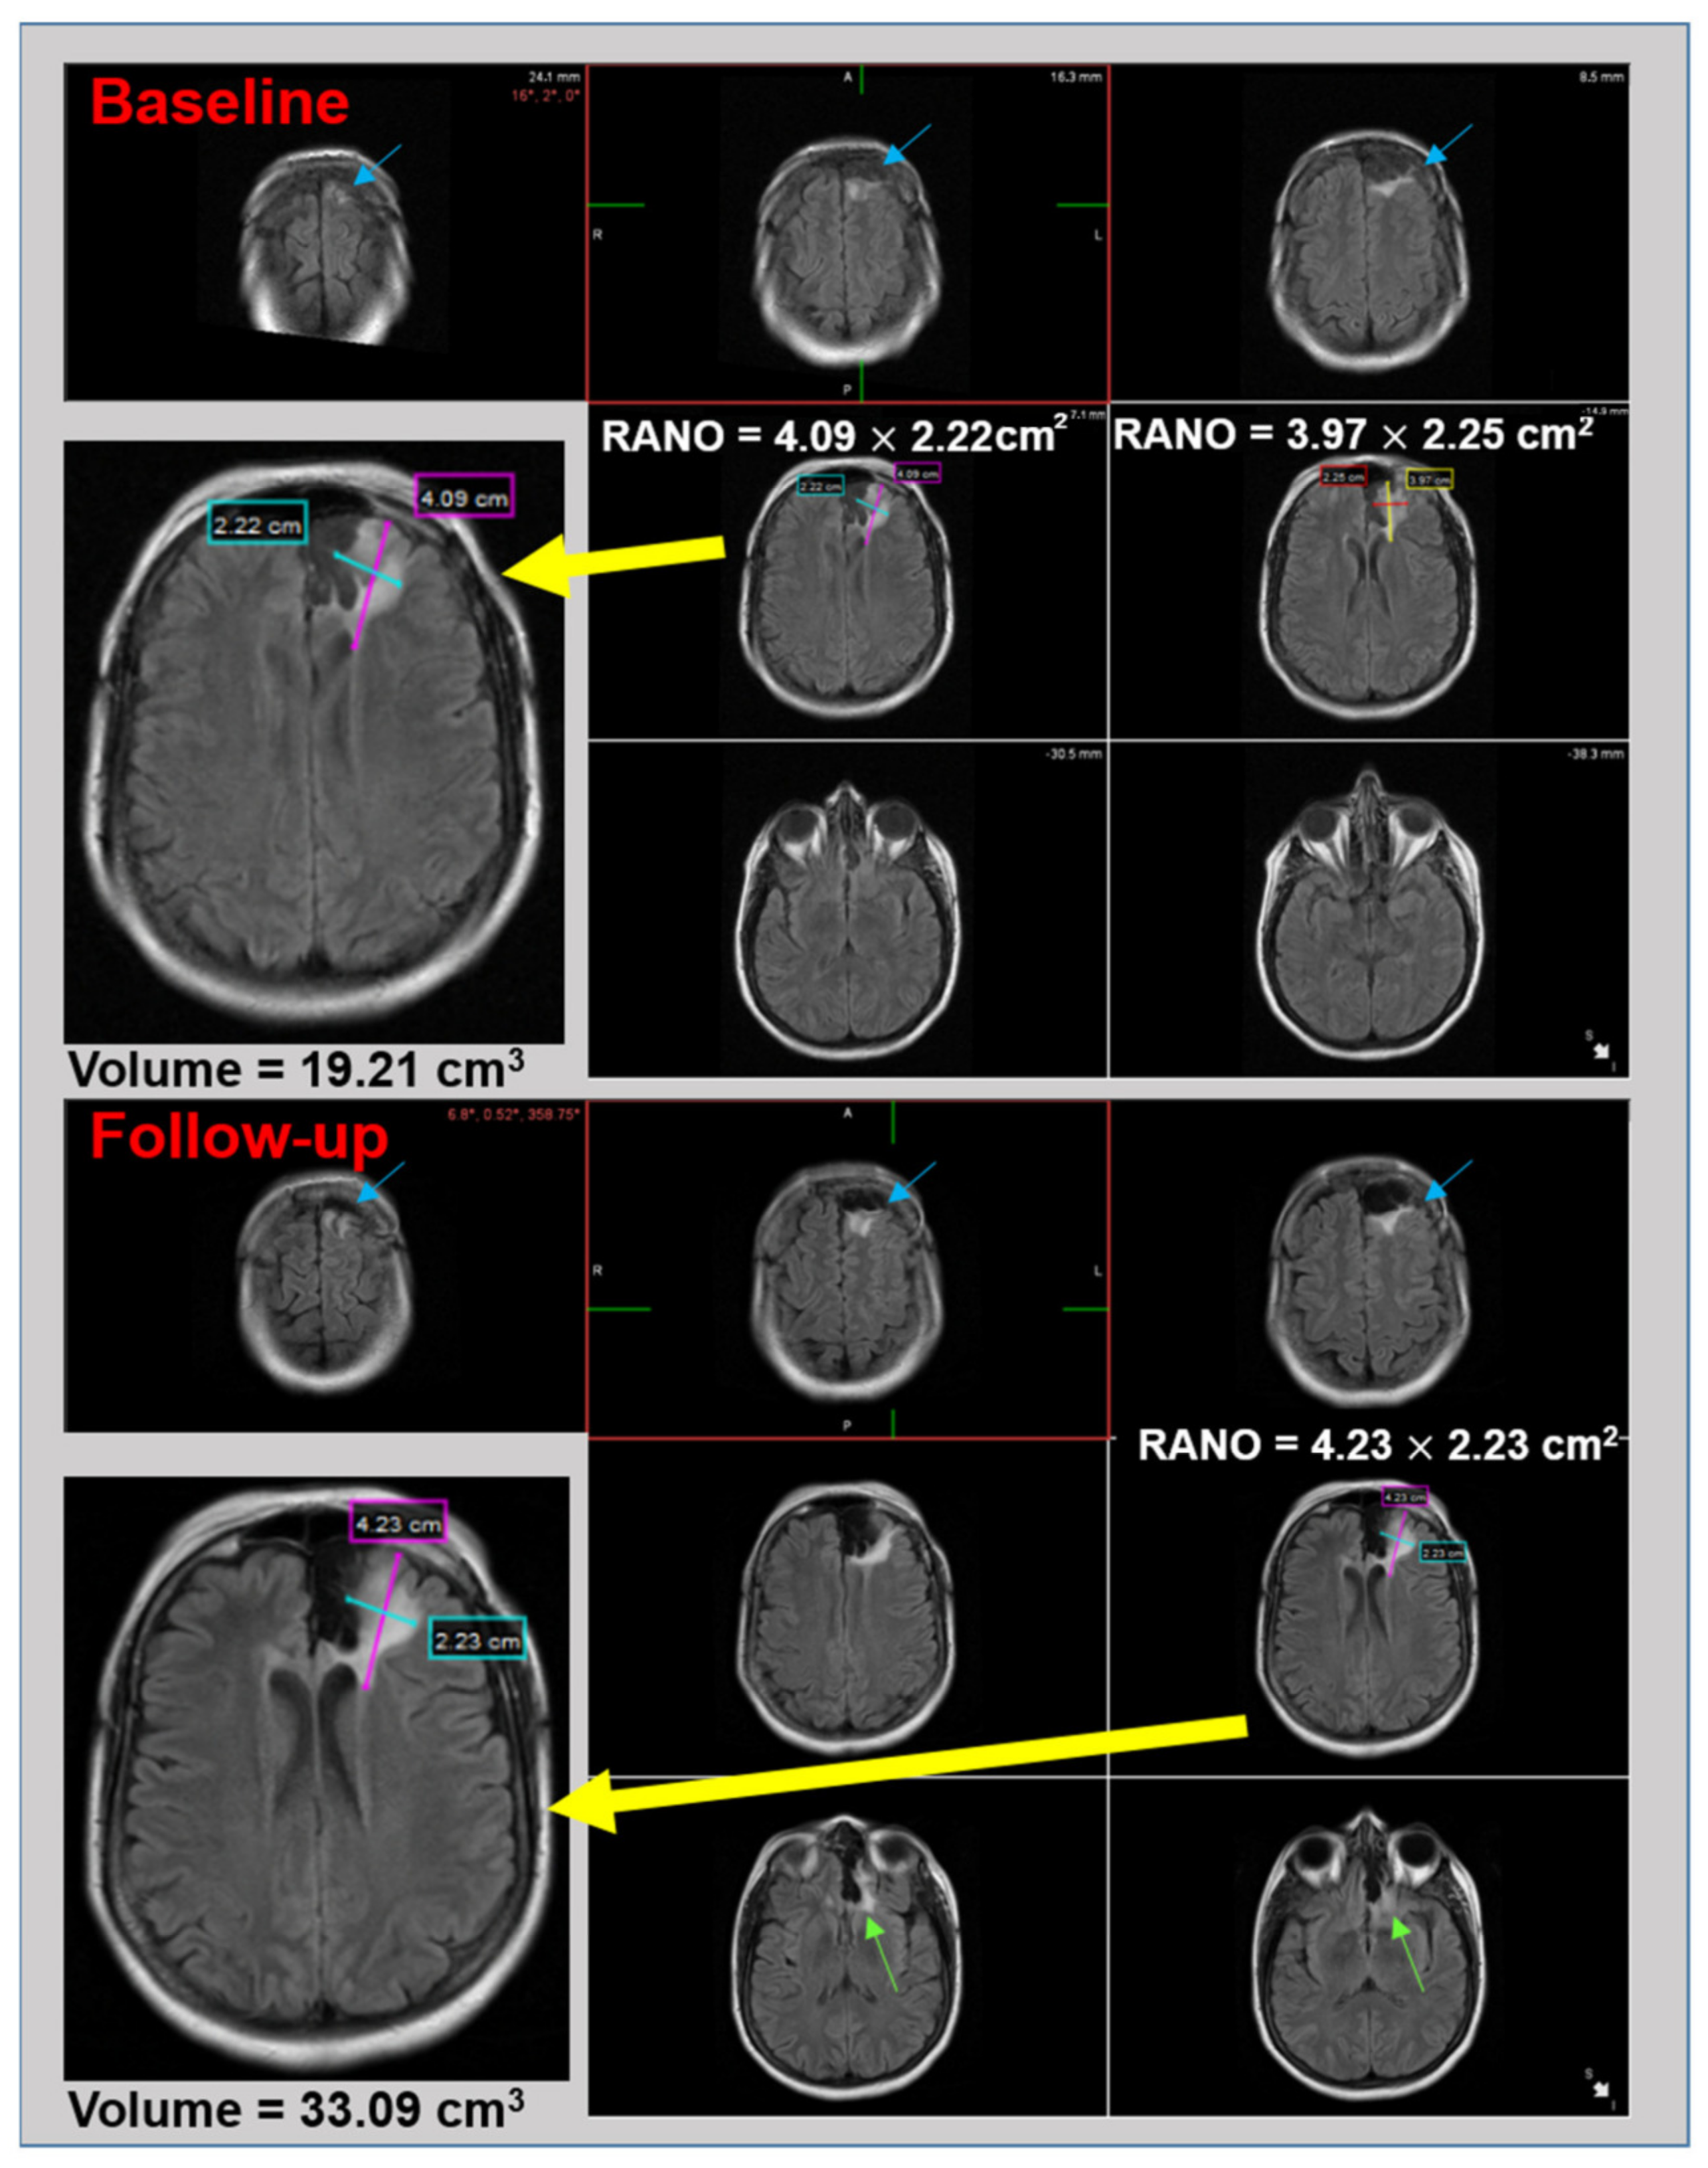

2.2. Image Analysis